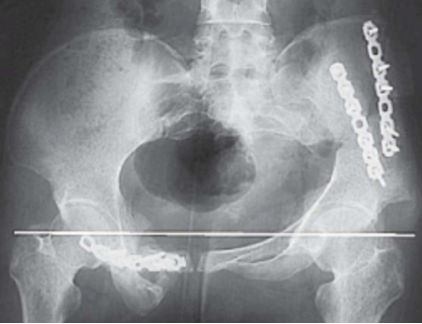

遂行左侧髂骨截骨重建钢板内固定,术后双下肢不等长减少到1 cm,X线检查显示双侧大粗隆大致在同一水平(图3)。

图3(图源:作者提供)